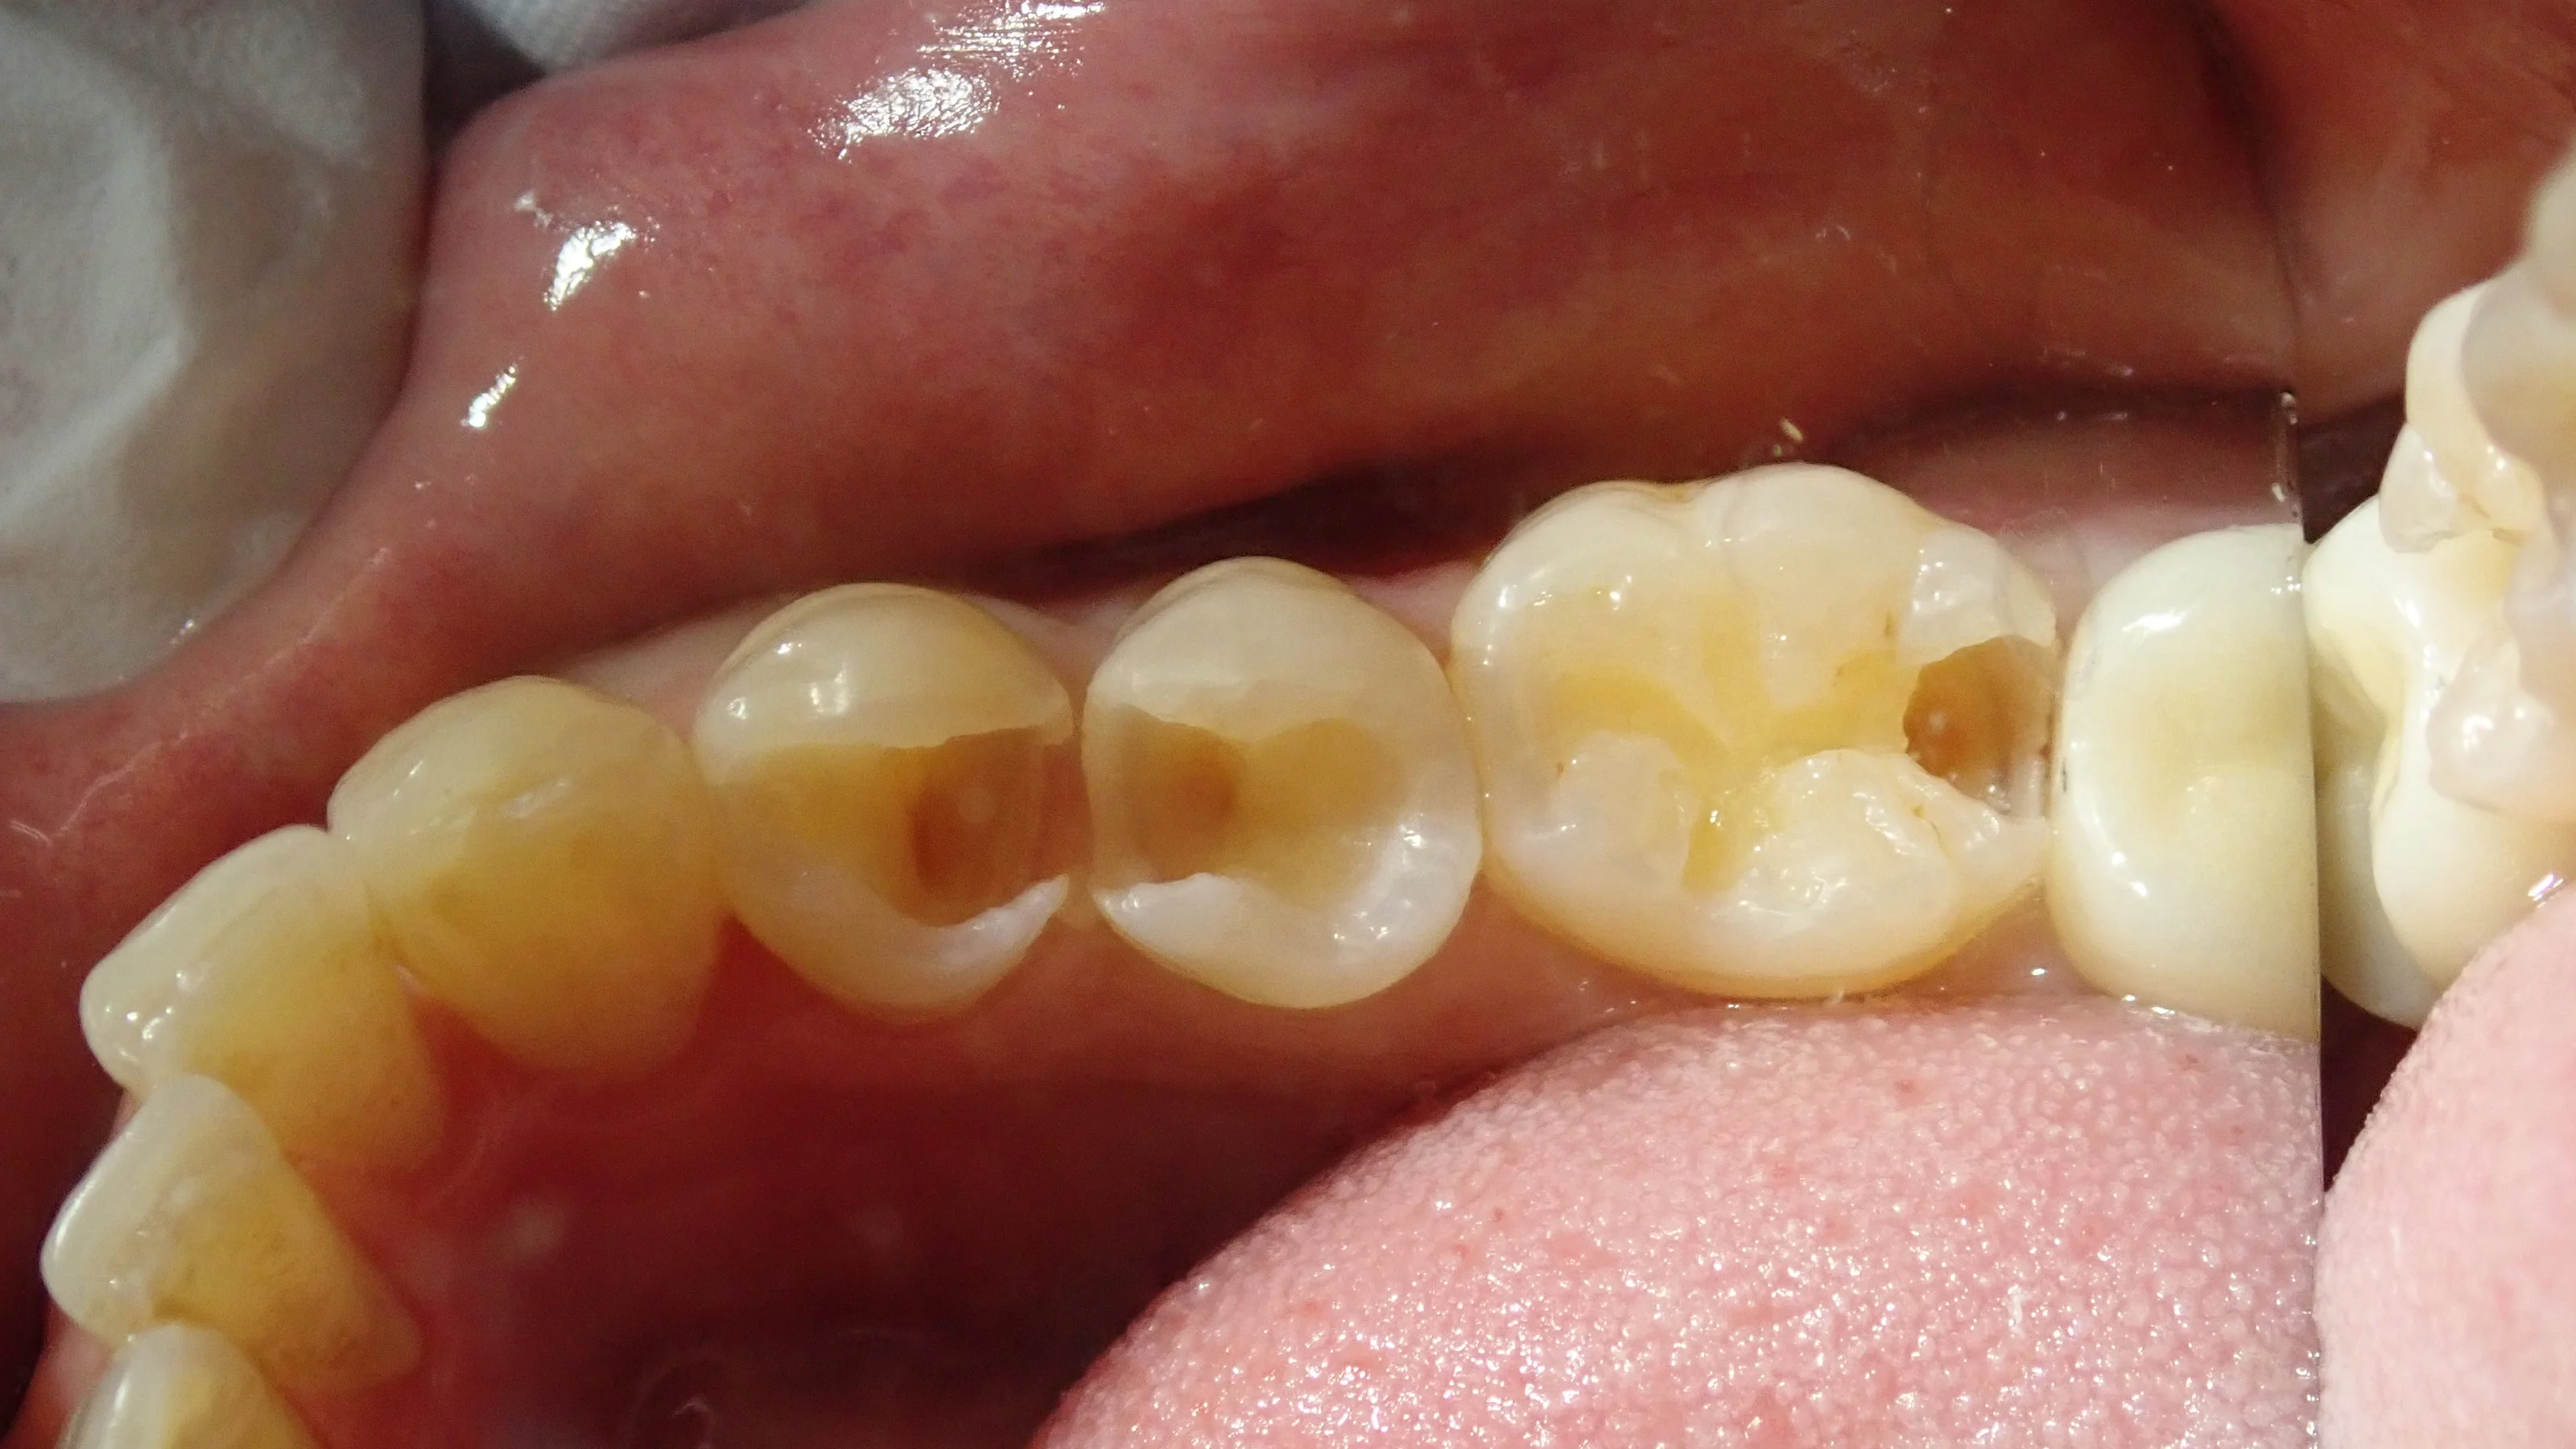

軽く古い詰め物を取ってみたのがこちらの写真です。

ここまで行くと真っ黒になっているのが分かりやすいですね・・・。

取りきったのがこちらの写真です。

手前二つは非常に大きく、神経ギリギリまで虫歯が進行していました。

着色が残っていますが、ここには色がついているだけで細菌は存在しない部分になります。

ここを取りきると神経への大きなダメージにつながるので、取ってはいけない部分でもありますね。

あまりにサイズが大きく、歯の半分はもうない状態で、表面のエナメル質という部分のみが残存している状態になります。